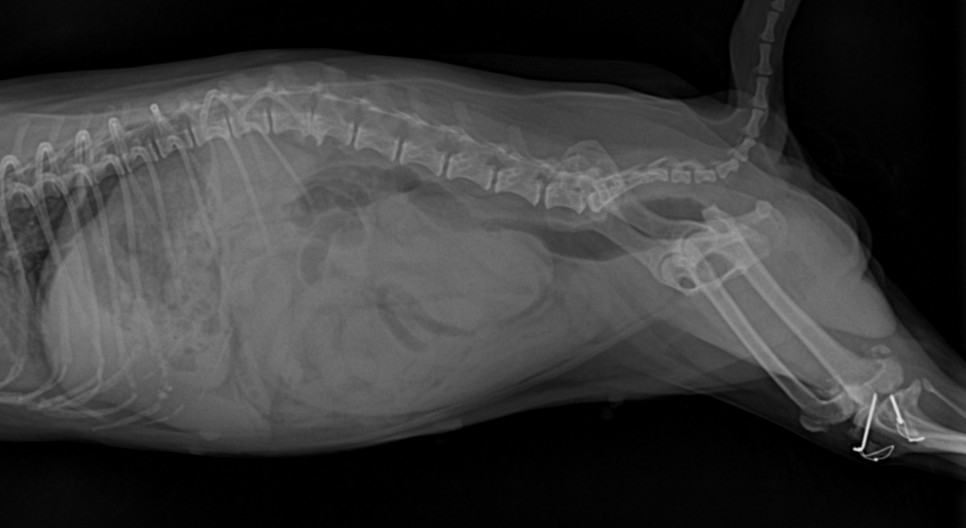

동물 병원에 내원해 주시고, 수의사의 판단으로 검사를 통해 확인이 됩니다.기본적으로 필요한 최소한의 검사는 복부 초음파 검사나 X 선 검사, 혈액 검사 등이 진단에 필요합니다.

신체 검사 결과 생식기 쪽에서 삼출물이 확인되었습니다.자궁 축농이 의심되는 상황이어서 초음파 검사를 통해 확진을 할 수 있었습니다.

초음파 검사를 통해 확장되어 있던 양쪽 자궁을 확인할 수 있었습니다